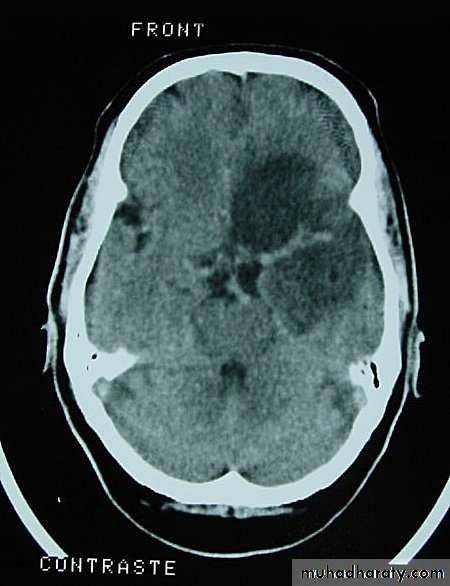

• On CT, they only show well with intravenous contrast.

Metastatic Brain Tumours

Metastatic Brain Tumours Pre contrast CT

Metastatic Brain Tumours Post contrast CT